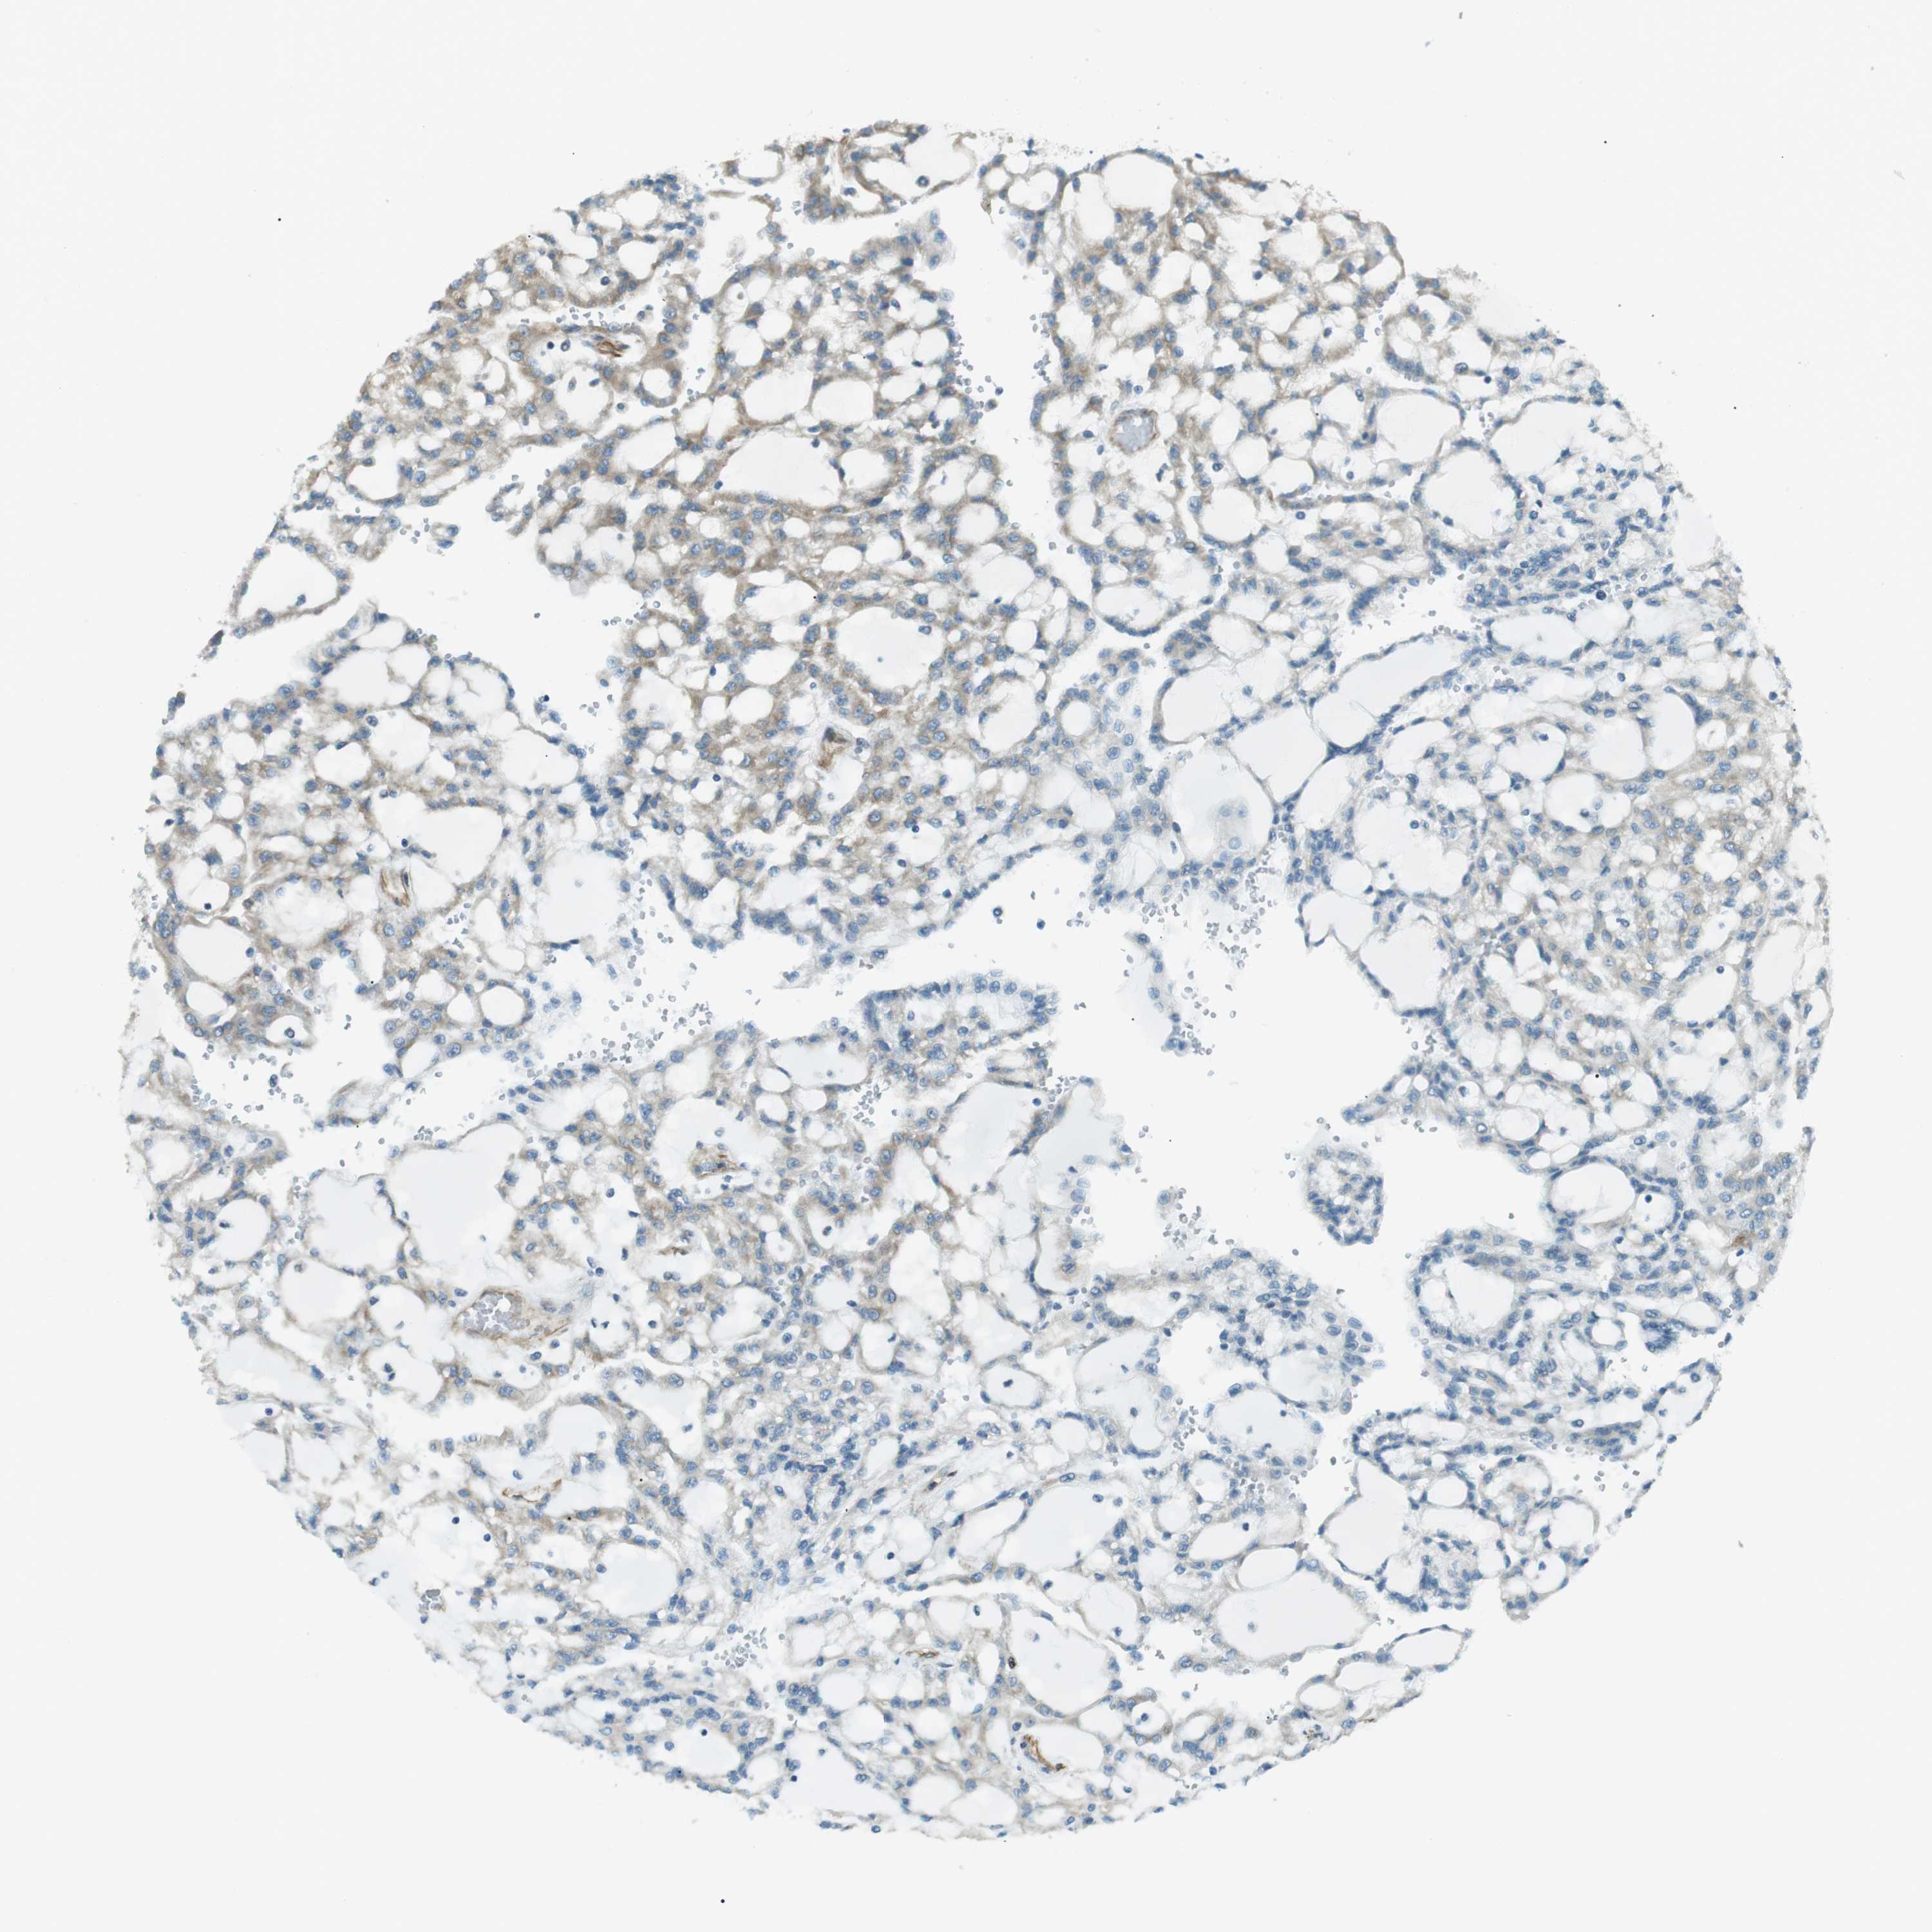

CANCER RENAL CANCER Show tissue menu

KICH TCGA KIRC TCGA KIRC VALIDATION KIRP TCGA PROTEIN RCC CPTAC PROTEIN EXPRESSION